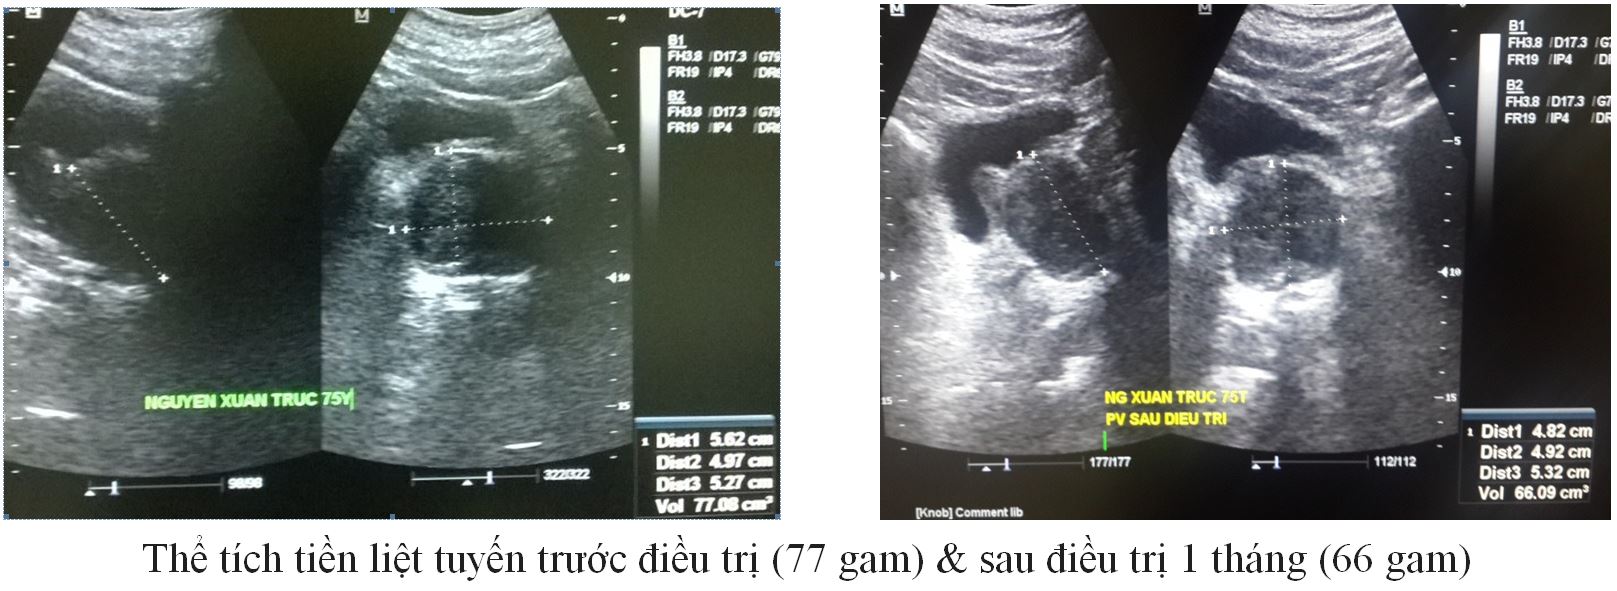

Trường hợp 4:

– BN: Tr, 75 Tuổi / Tiểu đường nhiều năm không mổ

– Tiểu khó, nhiều lần ( 4 lần trong đêm)

– Thể tích TLT 77 gam.

|

Trước ĐT |

Sau 1 tháng ĐT |

IPSS (Điểm) |

16 |

9 |

QoL (Điểm) |

3 |

2 |

PVR (ml) |

25 |

20 |

PV (gam) |

77 |

66 |

PSA (ng/ml) |

1,6 |

– |